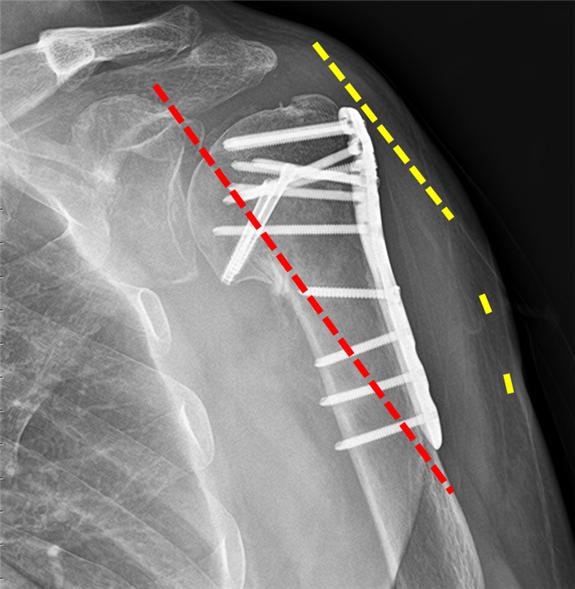

ÀÌ¿¡ ÇѸ²´ëÇб³µ¿Åº¼º½Éº´¿ø Á¤Çü¿Ü°ú ±è¿ëÅ ±³¼ö´Â Áö³­ÇغÎÅÍ À̹ø´Þ±îÁö 1³âÀÌ ³Ñ´Â ±â°£µ¿¾È ¼ö¼úÀÌ ÇÊ¿äÇÑ ¸ðµç ¾î±ú »ó¿Ï°ñ °ñÀýȯÀÚ ¾à 40¸íÀ» ÃÖ¼Ò Àý°³ °íÁ¤¼ú·Î Ä¡·áÇß´Ù. ±è ±³¼ö´Â ±âÁ¸ ¼ö¼ú¹ý°ú ´Þ¸® °ñÀýºÎÀ§¿Í °¡±î¿î ¾î±úÀÇ Ãø¸é¿¡ ¼Õ°¡¶ôº¸´Ù ªÀº Àý°³Ã¢À» ¸¸µé¾î Àý°³ºÎÀ§¸¦ ÃÖ¼ÒÈ­Çß´Ù. ÀÌÈÄ ½Ç½Ã°£ X-ray·Î ¼ö¼úºÎÀ§¿Í ½ºÅ©·ù »ðÀÔ °æ·Î¸¦ È®ÀÎÇϸç, »ó¿Ï°ñÀ» Áö³ª´Â ¾×¿Í½Å°æÀ» ÇÇÇØ °ñÀý ºÎÀ§¸¦ ±Ý¼ÓÆÇ°ú Àá±Ý³ª»ç·Î °íÁ¤½ÃÄ×´Ù. ±è ±³¼ö´Â ƯÈ÷ Ç÷¾×¼øÈ¯°ú »À À¯ÇÕ¿¡ µµ¿òÀÌ µÇ´Â °ñÀý ºÎÀ§ÀÇ Ç÷Á¾À» ³²°Ü³õ´Â ¹æ¹ýÀ¸·Î ºü¸¥ ȸº¹À» µµ¸ðÇß´Ù.

ÀÌ ¼ö¼ú¹ýÀÇ Æò±Õ Àý°³ Å©±â´Â 6cm·Î ±âÁ¸ ¼ö¼ú¹ýÀÇ Àý¹Ý¿¡ °¡±õ´Ù. °í·É ȯÀÚÀÓ¿¡µµ ºÒ±¸Çϰí Àç¿ø ¹× ȸº¹±â°£µµ °¨¼ÒÇß°í 4ÁÖÂ÷ºÎÅÍ °£´ÜÈ÷ ÆÈÀ» ¾²°í 6ÁÖÂ÷ºÎÅÍ ¸ðµç ÀÏ»ó»ýȰÀÌ °¡´ÉÇØÁ® ÀÚ°¡ ÀçȰġ·á¸¦ ½ÃÀÛÇÒ ¼ö ÀÖ¾ú´Ù. ¶ÇÇÑ ÃÖ¼Ò Àý°³ÀÇ ÀÌÁ¡À¸·Î °¨¿°, ºÒÀ¯ÇÕ, »ó¿Ï°ñµÎÀÇ ¹«Ç÷¼º ±«»ç µî ÇÕº´ÁõÀÌ ¹ß»ýÇÑ È¯ÀÚ´Â ÇÑ ¸íµµ ¾ø¾ú´Ù.